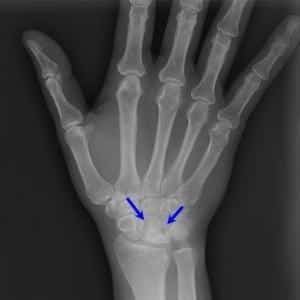

Для диагностики заболевания применяется комплексный подход. В него входит рентгенография, которая помогает обнаружить костные наросты, оценить степень сужения суставной щели, а также выявить уплощение и деформацию хрящей, разрушение костной ткани.